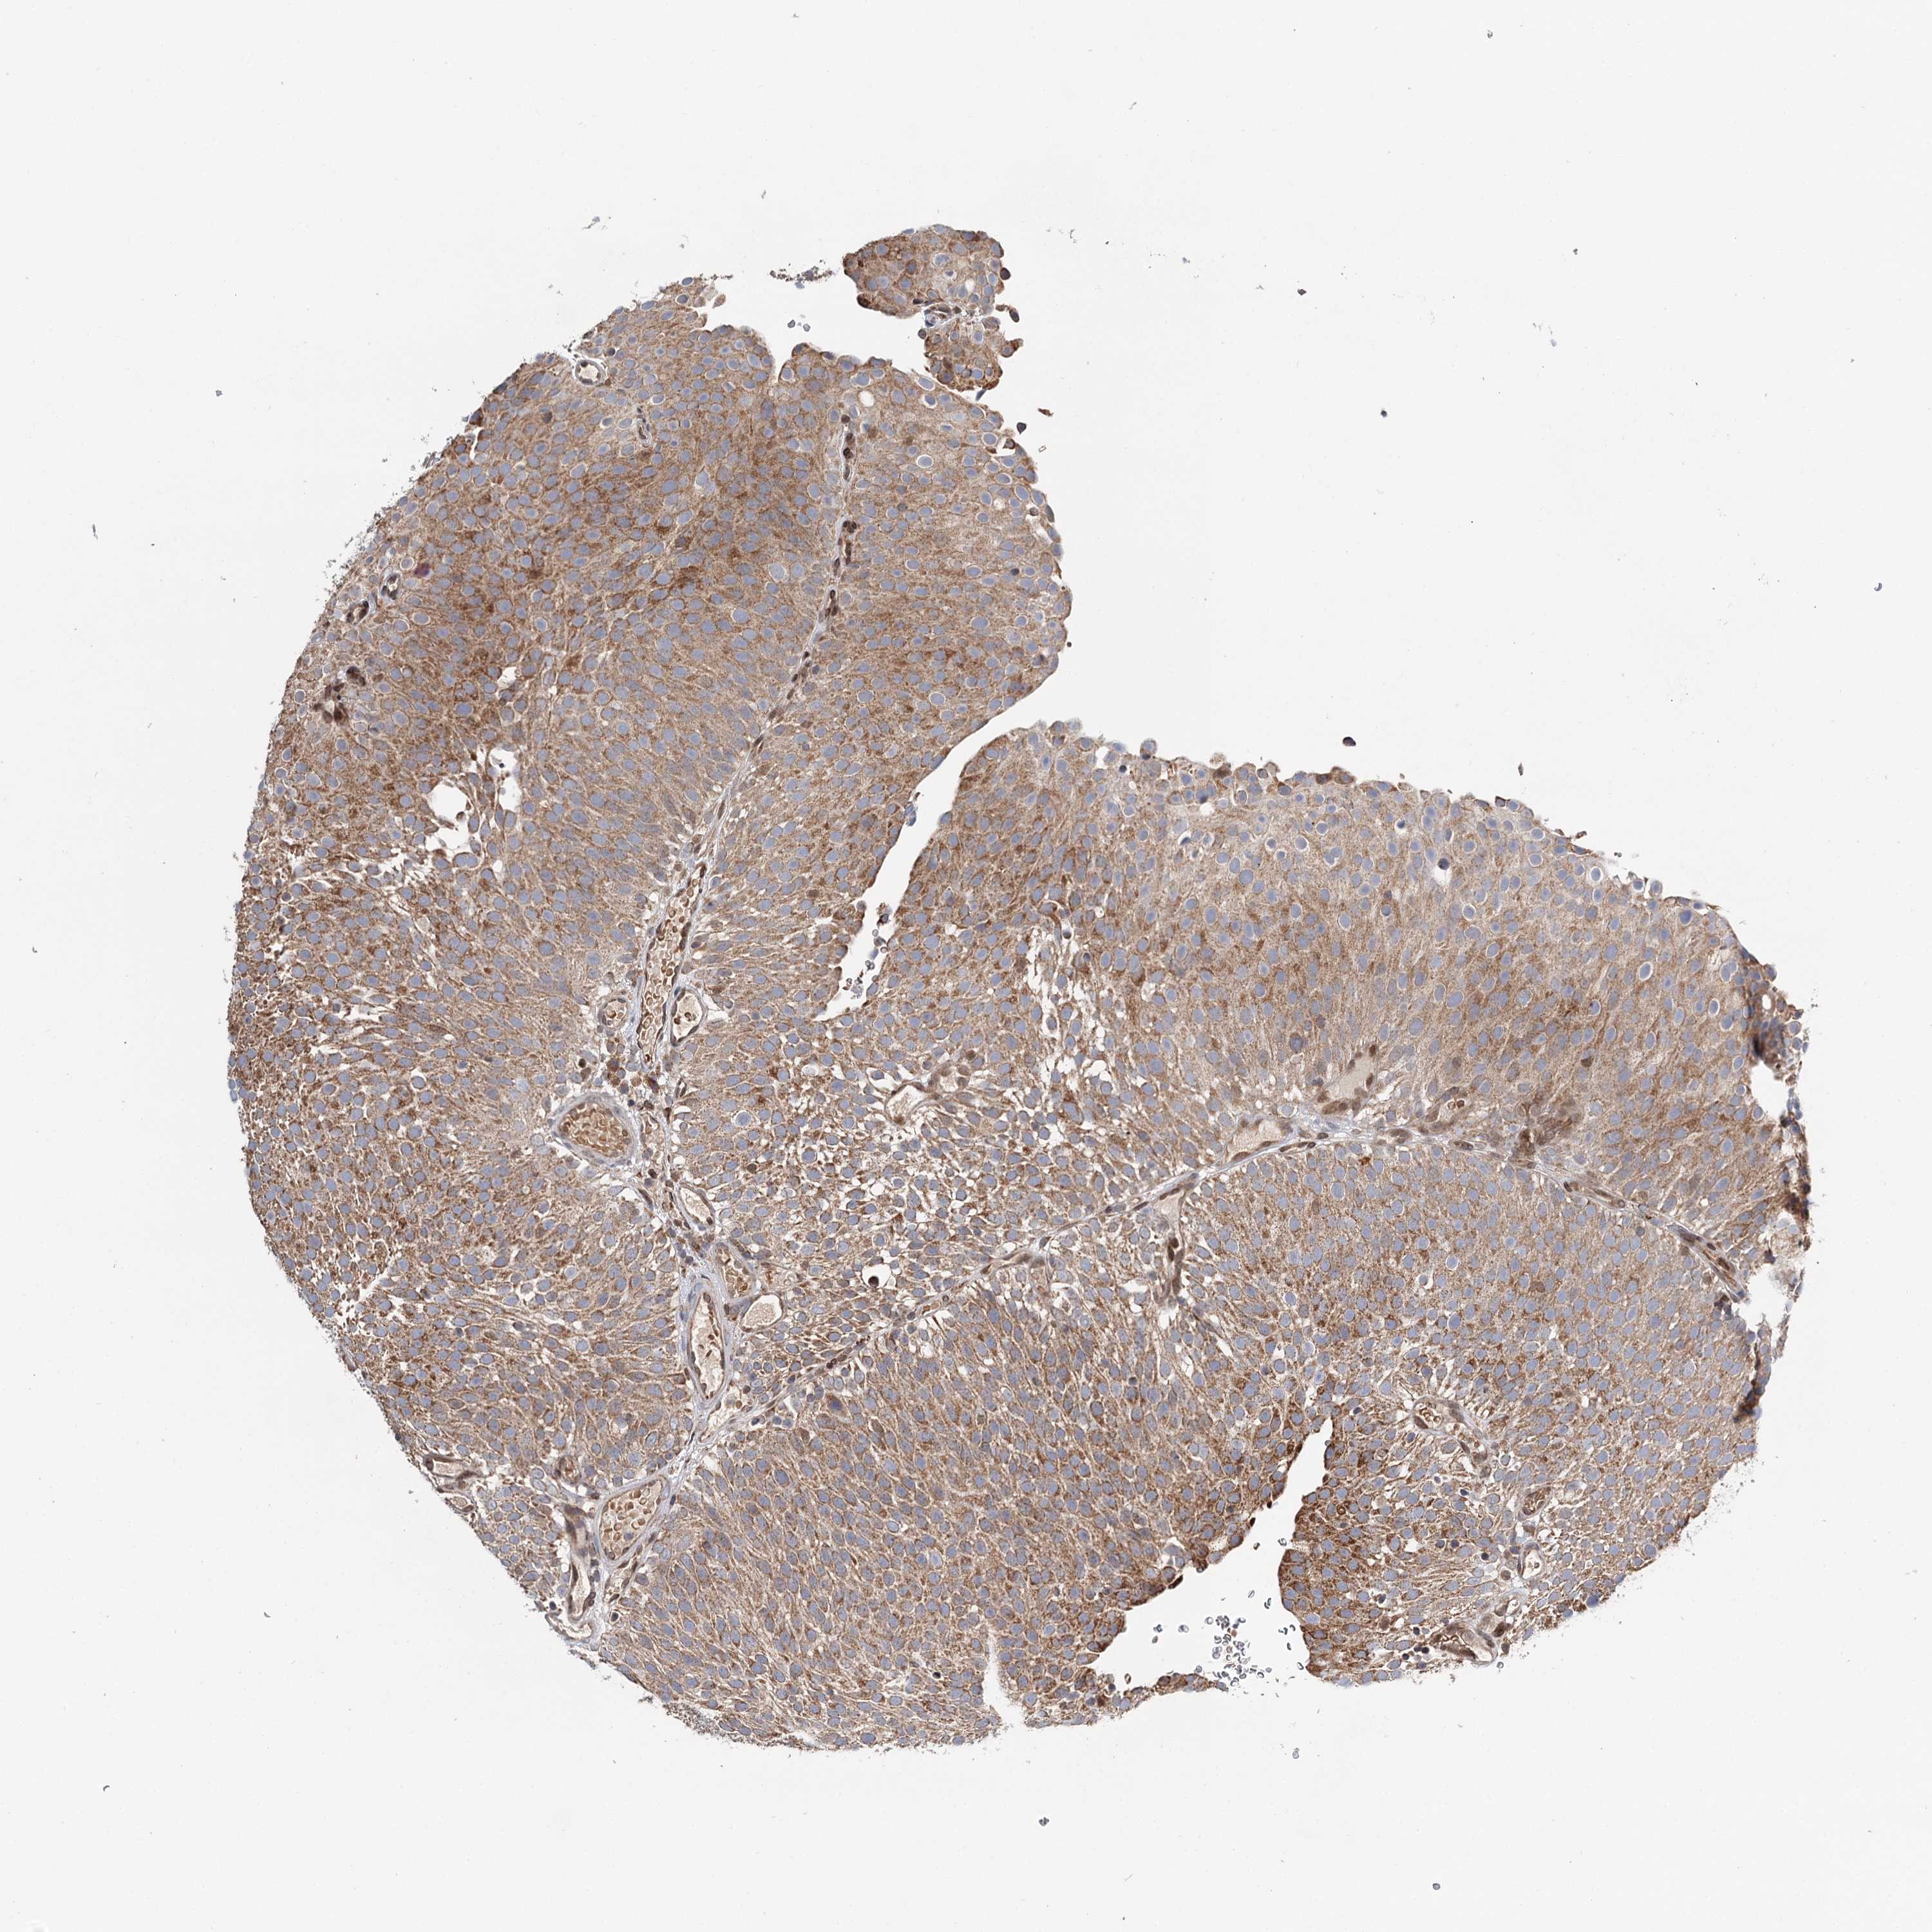

UROTHELIAL CANCER - Protein expressioni

A mouse-over function shows sample information and annotation data. Click on an image to view it in a full screen mode. Samples can be filtered based on level of antibody staining by selecting one or several of the following categories: high, medium, low and not detected. The assay and annotation is described here.

Note that samples used for immunohistochemistry by the Human Protein Atlas do not correspond to samples in the TCGA dataset.

Antibody stainingi

Antibody staining in the annotated cell types in the current human tissue is reported as not detected, low, medium, or high, based on conventional immunohistochemistry profiling in selected tissues. This score is based on the combination of the staining intensity and fraction of stained cells.

Each image is clickable and will lead to virtual microscopy that enables deeper exploration of all samples and also displays staining intensity scores, fraction scores and subcellular localization as well as patient and tissue information for each sample.

Antibody HPA037786

Antibody HPA038034

Antibody HPA038867

Antibody HPA038868

Staining

High

Medium

Low

Not detected

Intensity

Strong

Moderate

Weak

Negative

Quantity

>75%

75%-25%

<25%

None

Location

Nuclear

Cytoplasmic/membranous

Cytoplasmic/membranous,nuclear

Urothelial carcinoma, High grade

Urothelial carcinoma, Low grade

Urothelial carcinoma, NOS